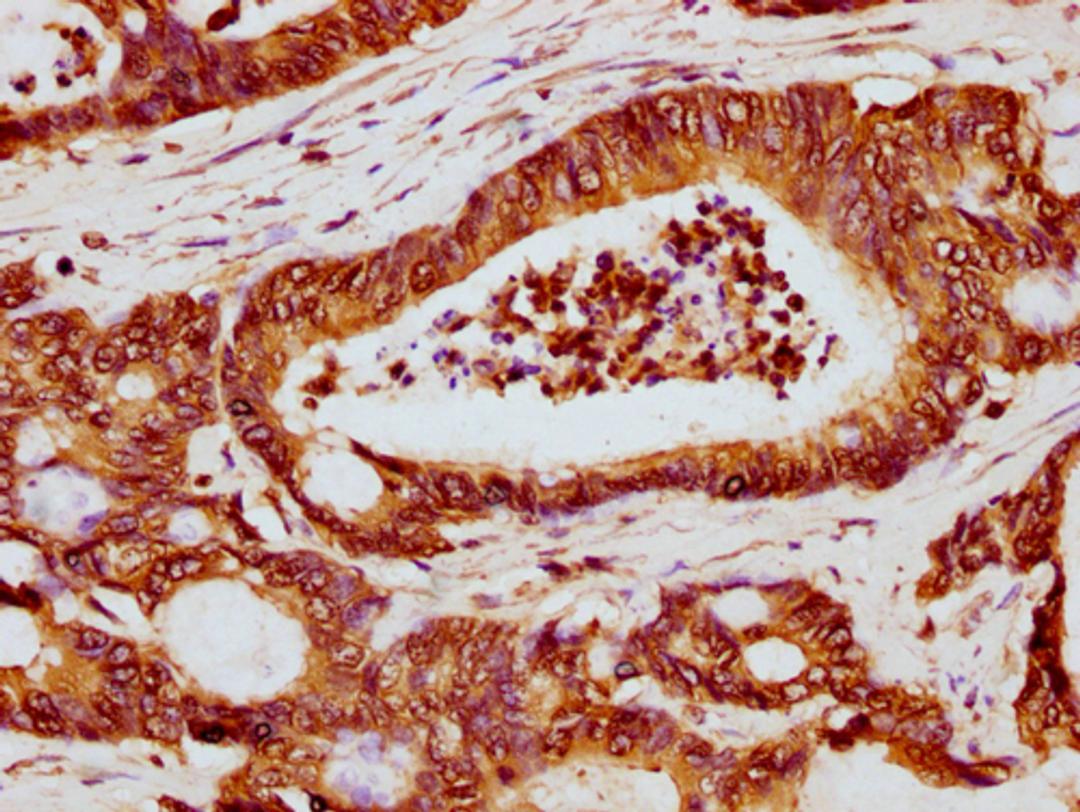

IHC image of CSB-PA010389OA119ncrHU diluted at 1:5 and staining in paraffin-embedded human colon cancer performed on a Leica BondTM system. After dewaxing and hydration, antigen retrieval was mediated by high pressure in a citrate buffer (pH 6.0). Section was blocked with 10% normal goat serum 30min at RT. Then primary antibody (1% BSA) was incubated at 4°C overnight. The primary is detected by a biotinylated secondary antibody and visualized using an HRP conjugated SP system.